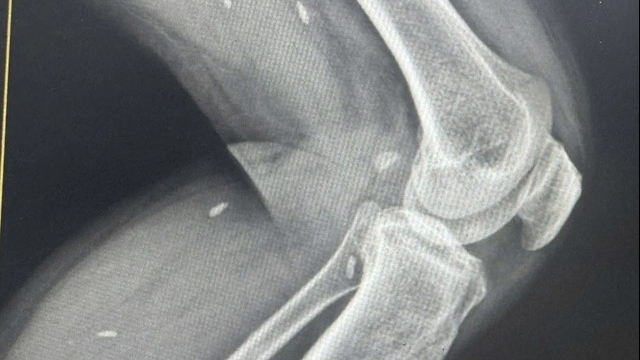

Điều trị trường hợp bệnh nhân bị tổn thương tắc động mạch cảnh trong sau tai nạn giao thông gây nhồi máu não diện rộng. |